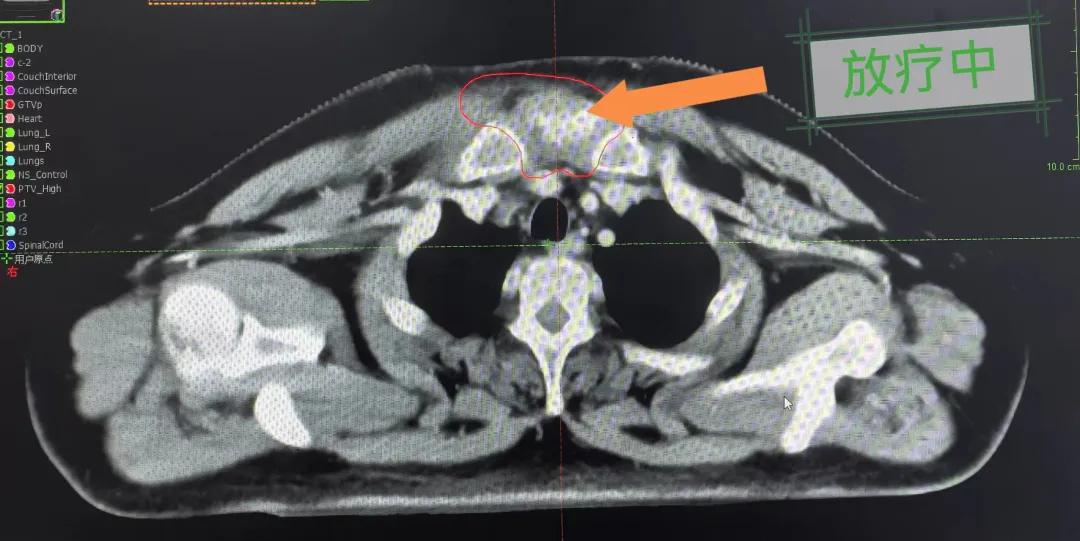

隨后,趙亮主任帶領放療團隊以最快的速度完成了患者的放射治療計劃,在保證放療精準打擊腫瘤的同時,利用先進的三維立體精確放療技術,最大限度的避免心臟、肺部的損傷發(fā)生,整體治療精準度達到1mm以內(nèi)。經(jīng)過10次的放射治療后,患者疼痛已明顯減輕,胸部腫物肉眼可見的縮小,患者及家屬臉上終于露出久違的笑臉。

治療期間,患者沒有出現(xiàn)明顯不適,治療結束后,患者胸壁腫物由最初8cm縮小至約1cm,后患者至外科行手術治療。